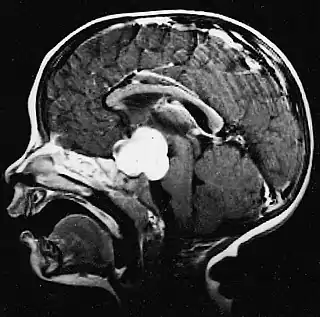

Este tumor se presenta generalmente como una lesión circunscrita y bien delimitada, de crecimiento lento y puede ser sólido o quístico.[2] Suelen apreciarse con facilidad en las imágenes de TC y RM. Los quistes pueden ser monoloculares o multiloculares, con el nódulo tumoral encapsulado en el interior. El astrocitoma pilocítico generalmente aparece a nivel del cerebelo, tronco cerebral, región hipotalámica, nervios y quiasma óptico, y en general en cualquier área donde haya presencia de astrocitos, incluyendo los hemisferios cerebrales y la médula espinal. La localización más frecuente es el cerebelo.[3]

El diagnóstico de este tumor se lleva a cabo normalmente usando la tomografía computarizada (TC) o la resonancia magnética nuclear (RM) del cráneo, con medio de contraste. De manera complementaria, puede añadirse una tomografía por emisión de positrones (PET).[8]

La RM ofrece una mayor sensibilidad en comparación con la TC, si bien no siempre es fácilmente accesible y presenta contraindicaciones, por ejemplo, no se puede utilizar en pacientes con marcapasos, prótesis incompatibles con el campo magnético, clips metálicos, etc. En las imágenes de TC y RM el astrocitoma pilocítico aparece como un tumor con márgenes bien definidos, redondeado, sólido o asociado a macro o microquistes. El 10 % presenta calcificación.[3] La captación de contraste es prácticamente homogénea y muy intensa. Este hallazgo es indicativo de una fuerte vascularización del tumor, aunque en este caso no se considera indicativa de malignidad. En fosa posterior, el diagnóstico diferencial se hace con el meduloblastoma, el ependimoma y el hemangioblastoma, y en la región quiasmática con el craneofaringioma.[9]